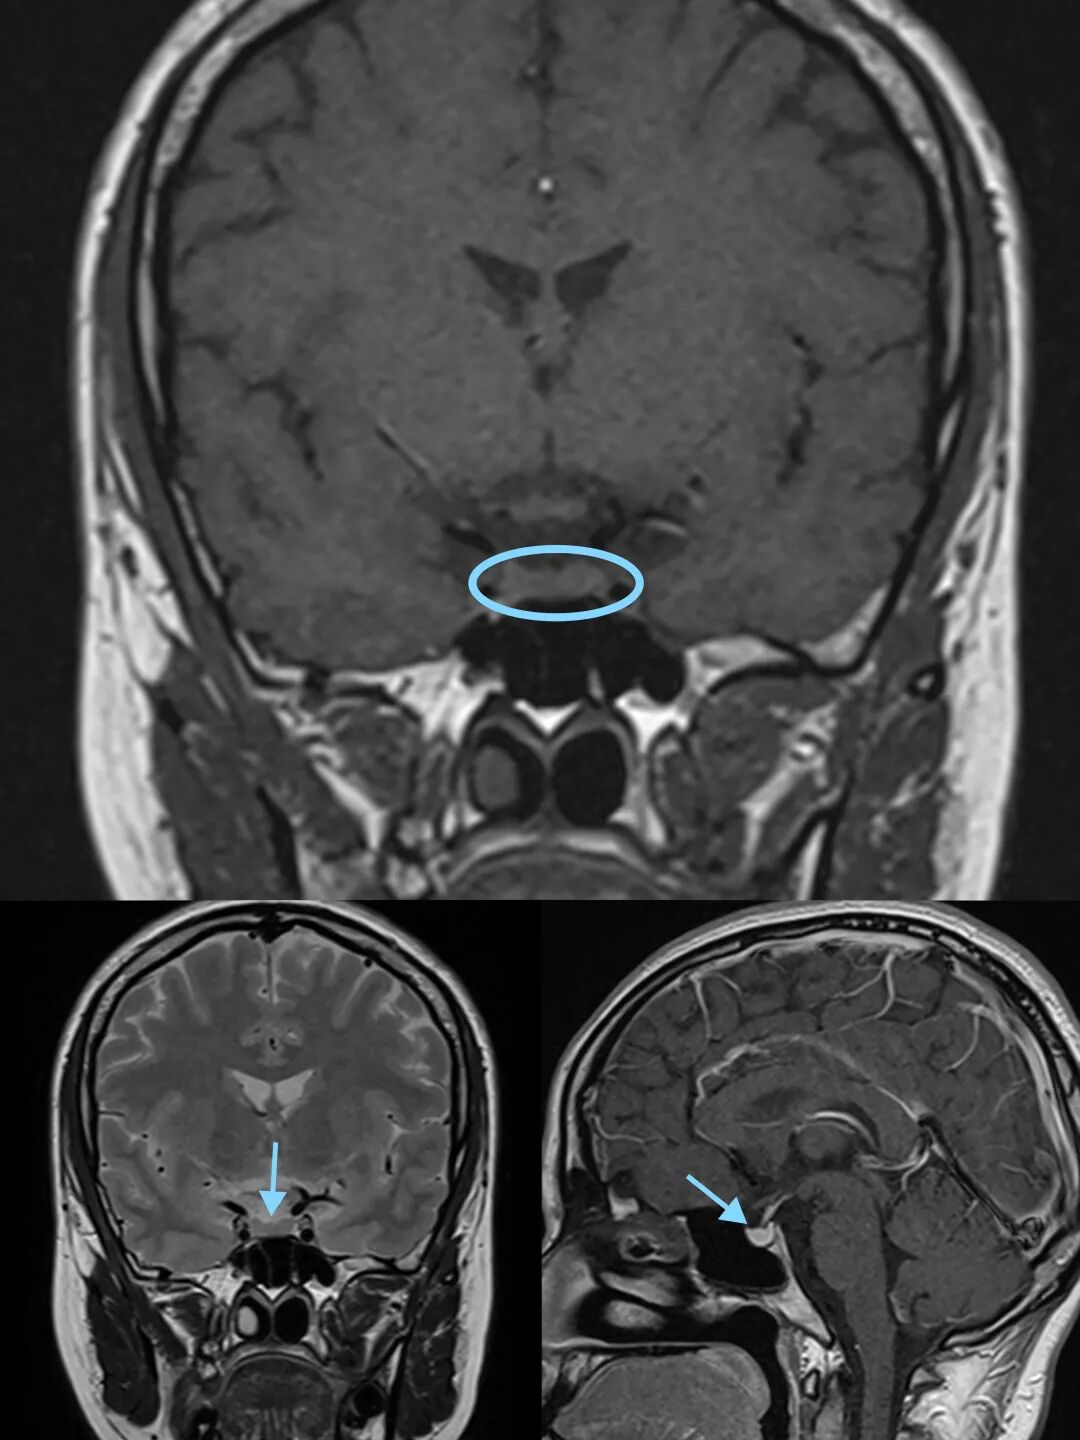

垂體呈一卵圓形的小體,在磁共振圖像上表現(xiàn)為橢圓形、信號(hào)均勻的結(jié)構(gòu),它位于顱底鞍區(qū)內(nèi)下丘腦的腹側(cè),可分為腺垂體(垂體前葉)和神經(jīng)垂體(垂體后葉)兩大部分。

垂體在MR中的形態(tài)及信號(hào)表現(xiàn)

磁共振成像(MRI)是一種無(wú)創(chuàng)性、無(wú)輻射的影像學(xué)檢查設(shè)備,具有軟組織分辨率較高的優(yōu)勢(shì);常規(guī)以垂體為中心對(duì)鞍區(qū)進(jìn)行橫斷位、冠狀位、矢狀位及動(dòng)態(tài)增強(qiáng)掃描得出圖像,可以全方位觀(guān)察垂體的形態(tài)、大小、信號(hào)等表現(xiàn),從而判斷正常或異常。當(dāng)垂體出現(xiàn)異常時(shí),將影響青少年的生長(zhǎng)發(fā)育。

從形態(tài)上的改變來(lái)說(shuō),當(dāng)垂體體積縮小時(shí),可能是垂體發(fā)育不良、垂體萎縮、空泡蝶鞍改變,而垂體增生、炎癥、出血、腫瘤,可導(dǎo)致垂體體積增大。垂體可分泌多種激素,當(dāng)垂體出現(xiàn)上述異常時(shí)將影響激素的產(chǎn)生與釋放。對(duì)于青少年的生長(zhǎng)發(fā)育來(lái)說(shuō),垂體發(fā)育不良會(huì)使生長(zhǎng)激素分泌減少,導(dǎo)致兒童生長(zhǎng)發(fā)育遲緩;當(dāng)垂體出現(xiàn)腫瘤,如垂體腺瘤,生長(zhǎng)激素分泌可以增多、也可以減少,導(dǎo)致兒童生長(zhǎng)發(fā)育提前或遲緩。